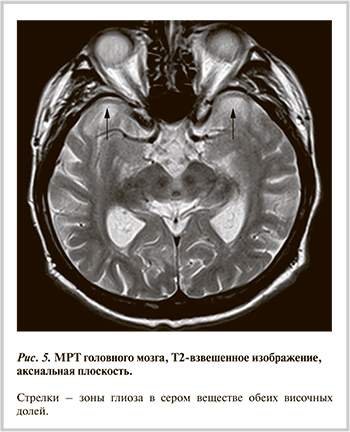

В связи с общемозговой симптоматикой и когнитивными нарушениями больному проведена МРТ головного мозга, по результатам которой выявлены множественные очаги в белом веществе головного мозга сосудистого генеза. Обращало на себя внимание наличие в передних отделах обеих височных долей зон повышенной интенсивности МР-сигнала неправильной формы с нечеткими неровными контурами, размерами 31×21 мм справа и 36×20 мм слева, которые были расценены как зоны глиоза (рис. 5). Кроме того, были выявлены признаки умеренно выраженной открытой внутренней гидроцефалии в виде расширения боковых желудочков мозга.

При телеметрическом контроле имплантируемого КД у пациента были выявлены также множественные продолжительные пароксизмы мерцательной аритмии (МА), большинство которых были бессимптомными. Принимая во внимание высокий риск развития тромбоэмболических осложнений у больных гипертрофической кардиомиопатией и наличие зон глиоза неясной этиологии в сером веществе обеих височных долей, пациенту начали антикоагулянтную терапию ривароксабаном в дозе 20 мг/сут. Учитывая отсутствие явных клинических проявлений, относительно невысокую частоту сокращений желудочков во время пароксизмов, органическое поражение сердца и сопутствующие нарушения проводимости, приняли решение воздержаться от поддерживающей антиаритмической терапии.